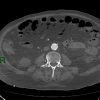

Nhồi máu ruột

» Thông tin: Nam giới – 85 tuổi.

» Lâm sàng: Đau bụng cấp.

# Dày thành ruột – Khí thành ruột – Khí tĩnh mạch mạc treo.